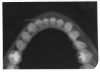

Bitewing examinations were introduced by Dr. Raper in 1925. Bitewing images focus on the clinical crowns of both the maxillary and mandibular teeth. Bitewings do not show the apices of the tooth and cannot be used to diagnose in this area. The greatest value of bitewing radio- graphic images is the detection of interproximal caries in the early stages of development, before it is clinically apparent. The arrows in Figure 2 indicate areas of interproximal caries. Bitewing images also reveal the size of the pulp chamber and the relative extent to which proximal caries have penetrated.

Bitewings also provide a useful adjunct to evaluating periodontal conditions. They offer a good view of the septal alveolar crest, and in addition, permit changes in bone height to be accurately assessed by comparison with adjacent teeth.

Figure 2 - Bitewing Images

Figure 2